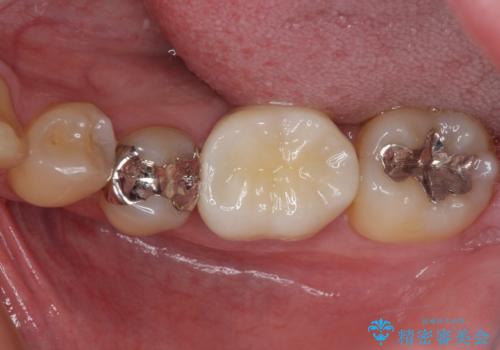

- 保険診療で装着した奥歯の白いクラウンの具合がよくないとのことで来院された患者様です。

保険診療で安価に白いクラウンが入れられるということで選択されたそうですが、装着後に痛みを感じたり、ものが挟まって不快であったりと不便が多いため、セラミッククラウンにて補綴治療を行うこととしました。

保険診療では、安価に白いクラウンを装着できる代償として、歯とクラウンの境目が不適合であったり、歯と歯の間にものが挟まりやすかったりと、不快な思いをされることがしばしばあります。

自費診療は、費用が高くなりますが、よい材料を選択したり、診療時間を十分にとったりできるため、単純に白いだけではない、良質なクラウンを装着することが可能です。